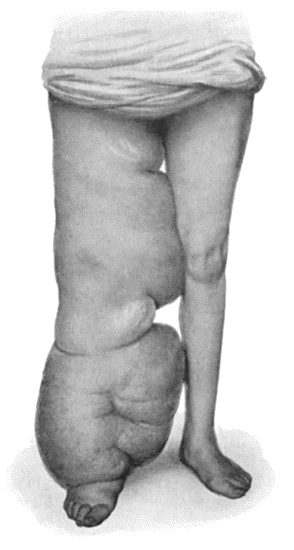

| 89. | Elephantiasis Neuromatosa in a woman æt. 28 | 359 |